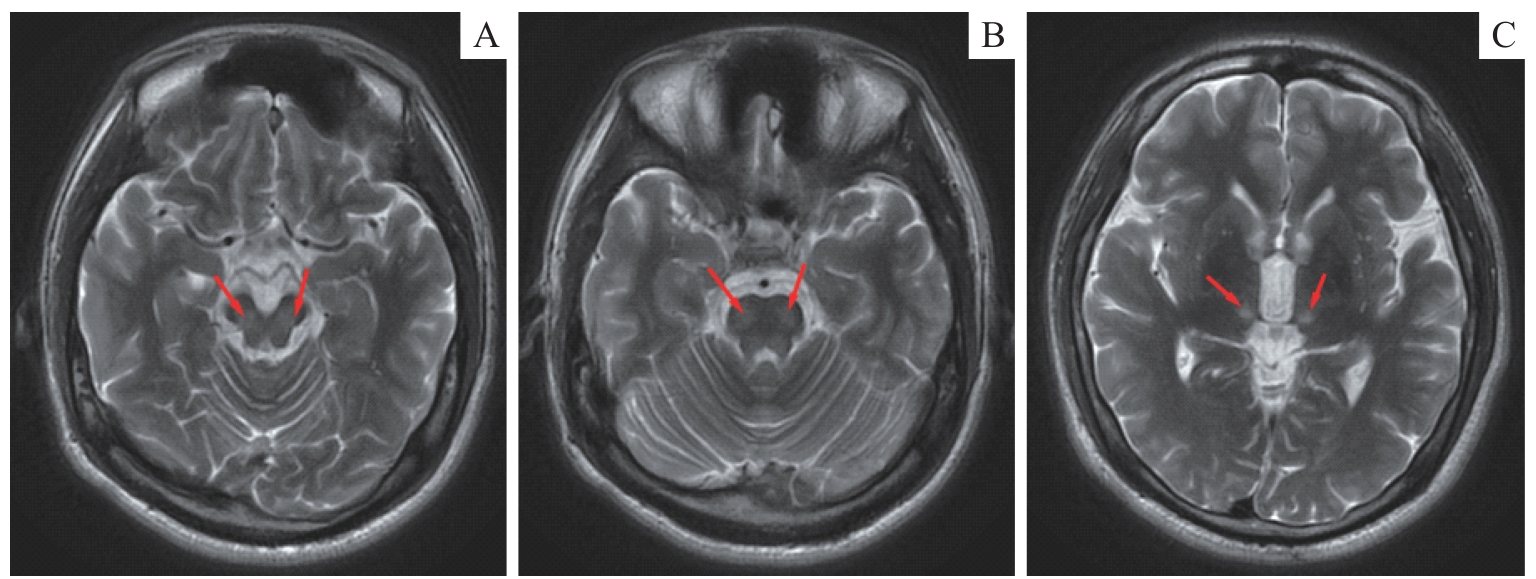

Tao Z, Zhou J F, Jiang Z Z, et al. Hepatolenticular degeneration-induced hepatic dysfunction with extremely atypical clinical manifestations: a case report[J]. Front Med, 2025, 12: 1599283.

|